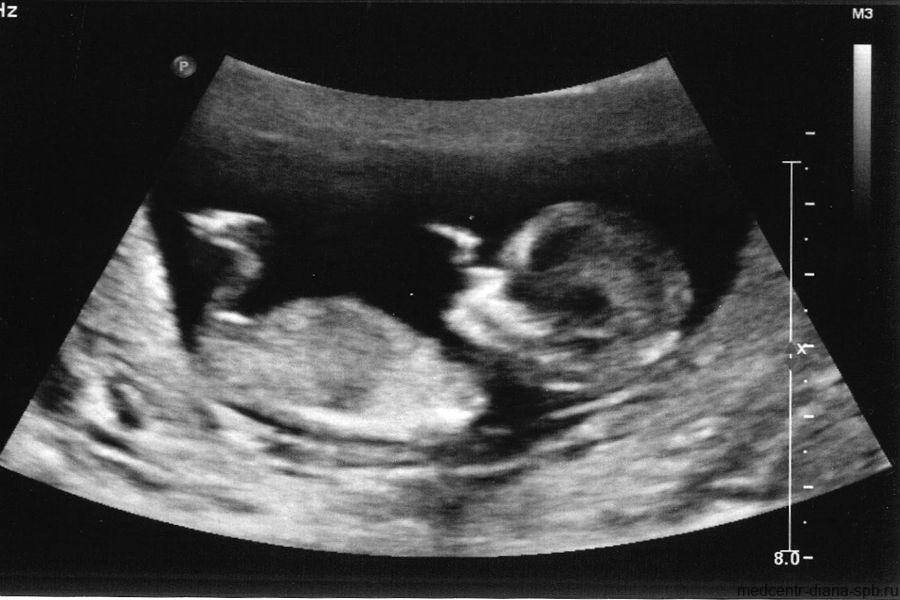

Фото УЗИ ребенка на 10 неделе беременности

На десятой акушерской неделе завершается закладка крупных внутренних органов. Вес малыша составляет уже 5 грамм. Хрящевая ткань при этом начинает уплотняться, превращаясь в костные структуры.

На фото УЗИ уже хорошо видны ручки и ножки малыша. Его голова несоизмеримо больше остального тела, а лобная часть явно выступает вперед. Пугаться этой особенности не стоит – это норма. Также на снимке можно отчетливо различить губы, нос и уши. Проводя ультразвуковое исследование, врач прослушивает сердцебиение, видит первые слабые движения конечностей. Также специалист может осмотреть строение позвоночника.